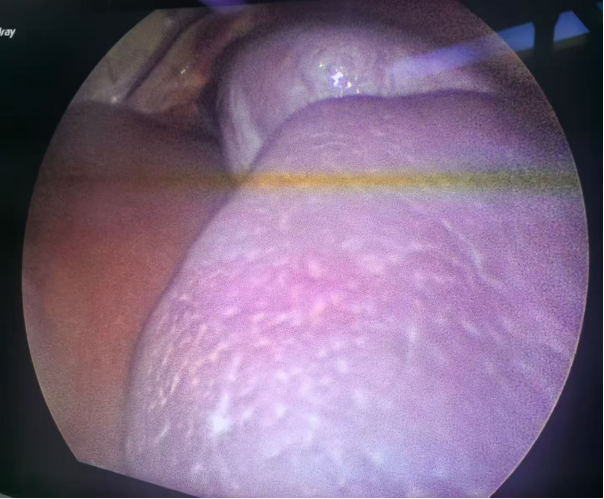

此次接受手术的患儿均为地中海贫血伴脾肿大,经小儿外科团队详细评估,患儿均符合脾切除手术指征,但考虑到儿童腹腔空间狭小、组织娇嫩,且家长对术后美观及康复速度有较高期待,团队决定采用“单孔腹腔镜技术”——仅在患儿脐部切开一个约2cm的小切口,通过专用器械完成脾脏游离、血管结扎及完整切除,最后将脾脏组织经脐部切口取出。

“单孔腹腔镜手术的关键在于‘精准’与‘协调’。”我院小儿外科主任窦俊锋介绍,脾脏血供丰富,周围毗邻胃、胰腺、结肠等重要器官,儿童腹腔操作空间仅为成人的1/3左右,术中需通过单一通道完成分离、止血、结扎等多步骤操作,对团队的解剖熟悉度、器械配合能力及应急处理水平要求极高。